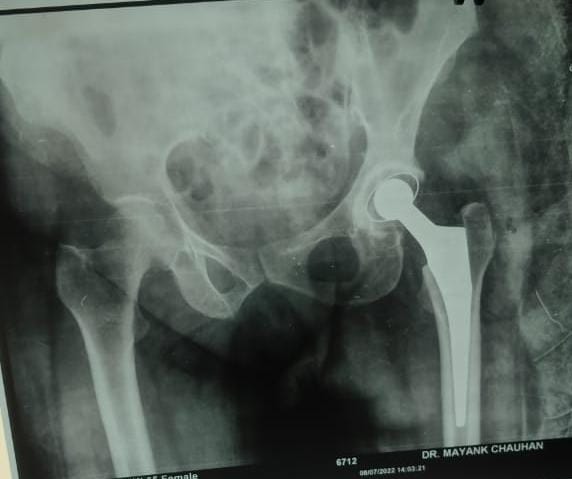

Hip replacement surgery is a procedure where damaged or diseased parts of the hip joint are removed and replaced with artificial components.